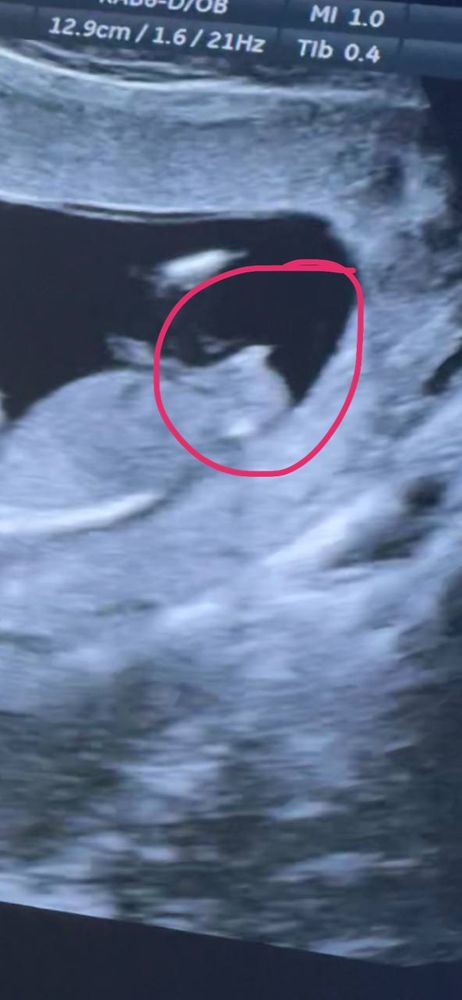

ну и ещё разок скину вам нашу фотку)) погадаем))